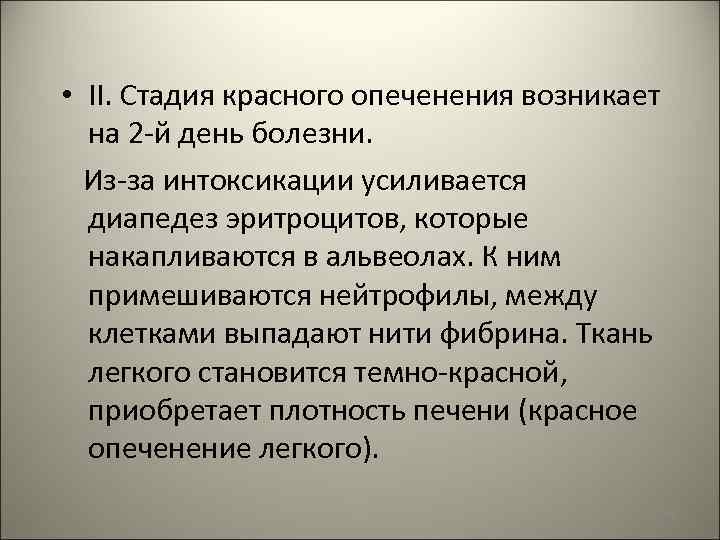

• II. Стадия красного опеченения возникает на 2 -й день болезни. Из-за интоксикации усиливается диапедез эритроцитов, которые накапливаются в альвеолах. К ним примешиваются нейтрофилы, между клетками выпадают нити фибрина. Ткань легкого становится темно-красной, приобретает плотность печени (красное опеченение легкого). 49

1225 – стадия красного опеченения легкого 50